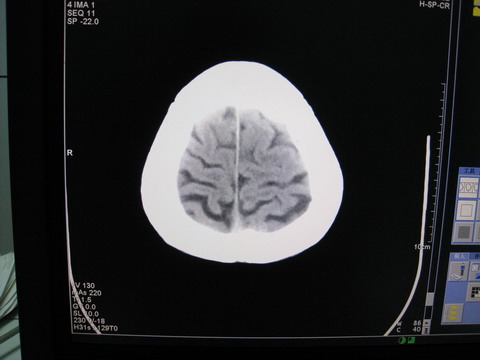

患者 男 69岁 头晕头痛不适

多发病灶,指状水肿,首先诊断转移瘤。

多个结节并周围大面积水肿区,多考虑多发性脑转移瘤

小病灶、大水肿,病灶多发,首先考虑多发转移瘤;建议查原发灶。

额顶叶多发小病灶、大水肿,首先考虑多发转移瘤;建议查原发灶

脑内多发病灶,小病灶,大水肿。

典型转移性肿瘤。

应进一步检查,查找原发病灶。

结果 : 该患者结肠癌病史5年 考虑脑转移